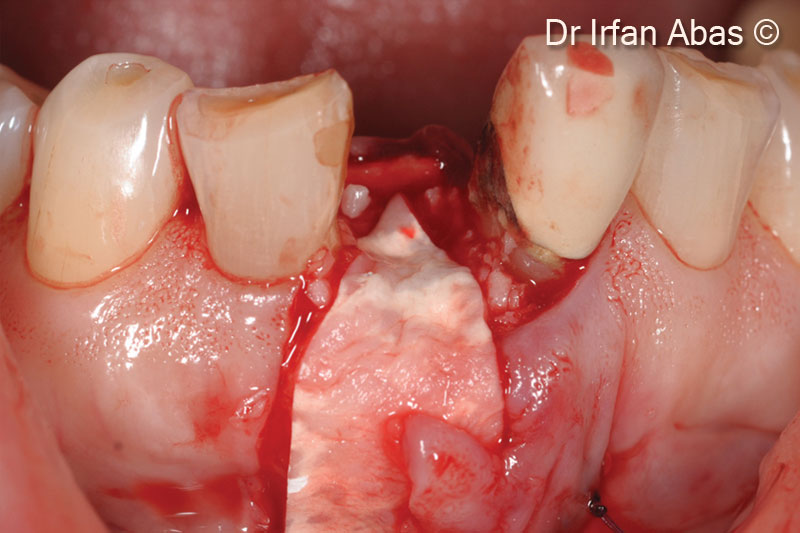

15.Newly formed bone before implant insertion

16. A Megagen mini-implant is inserted into newly formed bone